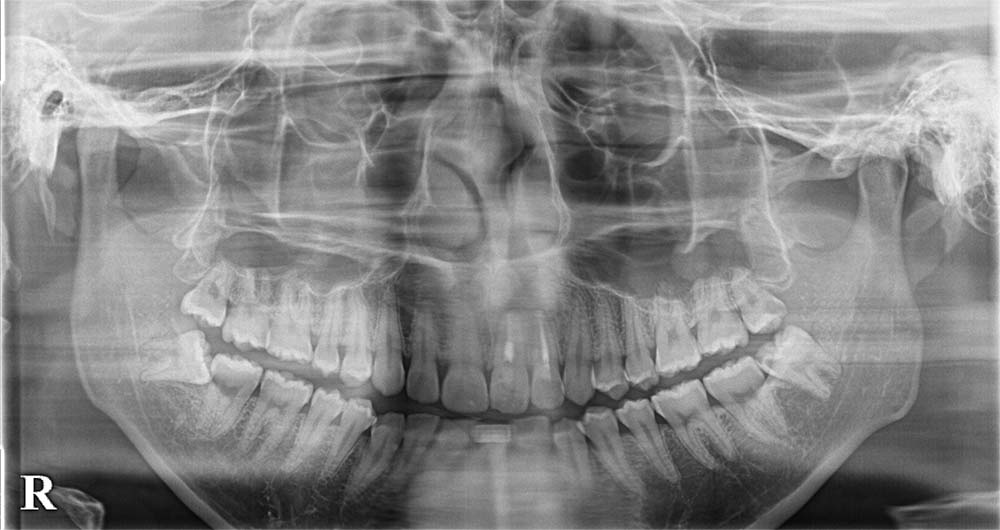

20代男性

ケース2:右下に食べ物がつまる

矯正治療中の患者さんですが、県内の歯科医院より紹介頂き受診されました。初診の当日に処置を行っています。

神経と歯の根が近かったためCTにて位置関係を3次元的に確認したうえで、5mm程度の切開を行い歯の頭の部分を削って抜きました。2糸縫って終わっています。

術後は紹介先で経過を診て頂いていますが、少しの腫れはあったようですが痺れ等はなかったようです。